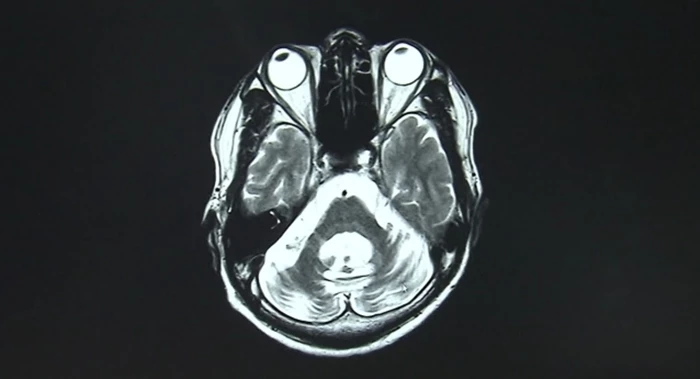

박 씨는 소뇌위축증을 앓고 있는 20대 후반 여성이다. '소뇌위축증'은 근육을 통제하는 힘을 서서히 잃어 말기에는 사망에 이르게 되는 무서운 병이다. 박 씨에게 남은 삶은 약 5년 정도다.

두려움에 대형병원에 가서 정밀 검사를 받아본 결과 우려대로 박 씨는 '소뇌위축증'이 발병했다는 진단을 받았다.

정확한 발병 원인과 치료제조차 알 수 없는 데다 평균 7년에서 10년 사이에 숨을 거두게 될 수 있고, 숨을 거두기까지 서서히 움직이지도 말을 할 수도 없게 된다는 설명을 들었다.